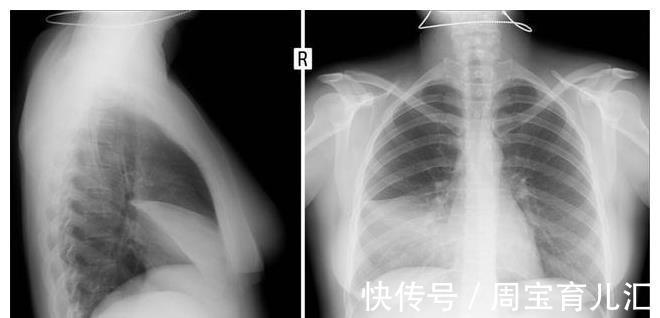

比如部分人肩膀持续疼痛一直没在意,在检查的过程中,却被告知肺部恶性肿瘤出现。那么,肺癌来临时会有哪些症状呢?

肩膀持续疼痛也是肺癌会有的信号,因为肺部的病灶不断发展,在肿瘤体积增大之后会牵拉或者压迫周围的组织、神经。除了肺部感觉到疼痛,身体其他部位可能也会产生疼痛感。

有不少人发病期间胸膜,胸壁被肿瘤侵犯,或者局部有胸腔积液,在影响之后肩膀偶尔也会产生疼痛感。如果并非肩膀部位的肌肉劳损或者关节病变引起,需要引起重视,通过检查判断是否肺部恶性肿瘤来袭。

肺癌不是小疾病,出现相关的疾病信号应该马上处理。那些明显咳嗽的人很可能是疾病在发展,说明肺部的病灶已经带来影响。随着癌细胞的入侵肺部功能下降情况越发明显,可能会有阻塞性肺炎、肺不张、胸内合并症出现。加上支气管粘液分泌改变,影响下患者就容易咳嗽,可能会有剧烈的刺激性干咳。有这种情况也得谨慎对待,判断是否肺癌出现。

【 病灶|肺癌来临,身体会“说话”?这4个都可能是警告,别大意】其实,引发声音嘶哑的原因较多,不同病因引发的声音嘶哑应对方式不同。如果是肺癌在发展,局部的病灶威胁着身体健康,喉返神经受到压迫,在声带麻痹之后声音嘶哑表现就明显,有这个症状需要谨慎,通过积极的治疗来控制肺癌发展。